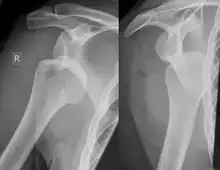

Diagnosis can be suspected by history and physical examination which is usually followed by imaging. Because of the mechanism of injury, apprehension of anterior dislocation is common with provocative maneuvers. Hill–Sachs lesions have been classified as "engaging" or "non-engaging", with engaging lesions defined by the ability of the glenoid to sublux into the humeral head defect during abduction and external rotation. Engaging dislocations have a higher risk of recurrent anterior dislocation, and their presence can help guide surgical management.[2] Imaging diagnosis conventionally begins with plain film radiography. Generally, anteroposterior (AP) radiographs of the shoulder with the arm in internal rotation offer the best yield while axillary views and AP radiographs with external rotation tend to obscure the defect. However, pain and tenderness in the injured joint make appropriate positioning difficult and in a recent study of plain film x-ray for Hill–Sachs lesions, the sensitivity was only about 20%. i.e. the finding was not visible on plain film x-ray about 80% of the time.[3]

By contrast, studies have shown the value of ultrasonography in diagnosing Hill–Sachs lesions. In a population with recurrent dislocation using findings at surgery as the gold standard, a sensitivity of 96% was demonstrated.[4] In a second study of patients with continuing shoulder instability after trauma, and using double contrast CT as a gold standard, a sensitivity of over 95% was demonstrated for ultrasound.[5] It should be borne in mind that in both those studies, patients were having continuing problems after initial injury, and therefore the presence of a Hill–Sachs lesion was more likely. Nevertheless, ultrasonography, which is noninvasive and free from radiation, offers important advantages.

MRI has also been shown to be highly reliable for the diagnosis of Hill-Sachs (and Bankart) lesions. One study used challenging methodology. First of all, it applied to those patients with a single, or first time, dislocation. Such lesions were likely to be smaller and therefore more difficult to detect. Second, two radiologists, who were blinded to the surgical outcome, reviewed the MRI findings, while two orthopedic surgeons, who were blinded to the MRI findings, reviewed videotapes of the arthroscopic procedures. Coefficiency of agreement was then calculated for the MRI and arthroscopic findings and there was total agreement ( kappa = 1.0) for Hill-Sachs and Bankart lesions.[6]